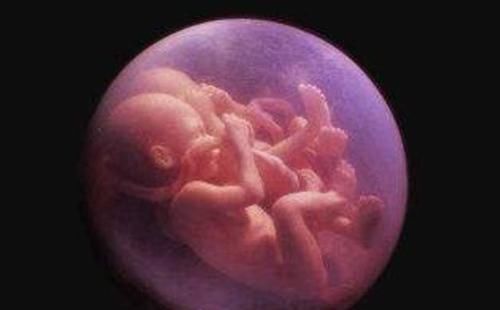

终于到了分娩这天,丈夫主动提出要陪产,因为是初产妇,小青生娃的时间比较长。过去了大半天的时间,小青终于在医护人员的指导下,顺利生下了一个可爱的宝宝,但没想到孩子出生后却自带金钟罩。因为小宝宝刚出生的时候,外面包裹着一层透明的壳,看上去就像一层保护罩。

对此产妇很是不解:难道我生了个哪吒,而小青的丈夫也被小婴儿的模样吓坏了,特别着急,以为孩子是身体方面有疾病,一时之间没有忍住悲伤的情绪,眼泪直接掉了下来。而护士看到宝宝的模样之后却连连道喜,护士告诉家人,小宝宝的这种情况很正常,说明身体非常健康,没必要担心。

而这层保护罩其实就是羊膜,它可以起到保护小婴儿的作用。